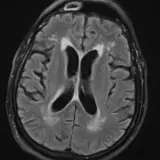

Neuro MRI

Neurodegenerative